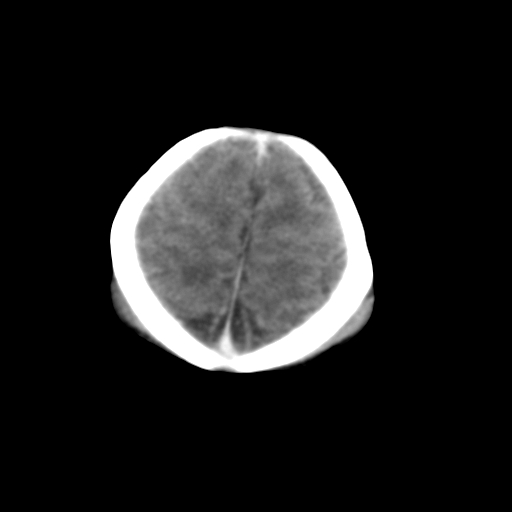

新生儿女2天,有窒息史,经抢救好转!白质最低ct值>23hu,请教各位老师:是否有出血?是否合并缺氧脑病?谢谢!

双侧额叶白质低,白质ct值低于18hu可以考虑水肿改变

后纵裂密度高,前纵裂密度低,比较来说应该考虑有蛛网膜下腔出血